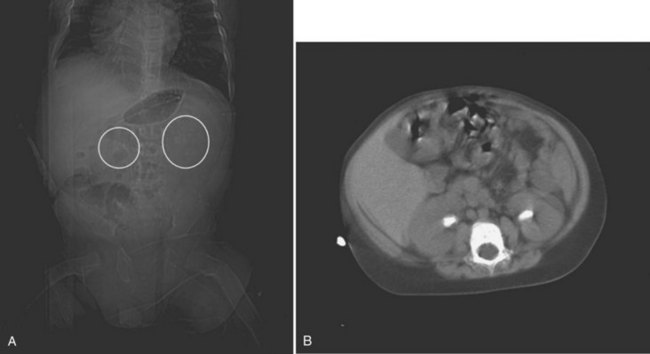

Figure 135–12 A 22-month-old boy with intractable diarrhea of infancy from tufting enteropathy who awaited a small bowel transplant. His risks for nephrolithiasis included total parenteral nutrition dependency, osteomalacia, chronic dehydration, hypocitruria, and hyperoxaluria. A, A kidney-ureter-bladder film demonstrated mildly radiopaque stones, and a subsequent CT scan (B) confirmed bilateral staghorn calculi. C, Prone view of left retrograde pyelogram of child in A, demonstrating staghorn calculi as a filling defect (arrow). A “mini-perc” technique was used to address his stones. D, Prone view of the antegrade nephrostogram through a 6-Fr nephrostomy tube demonstrating “stone-free” status.